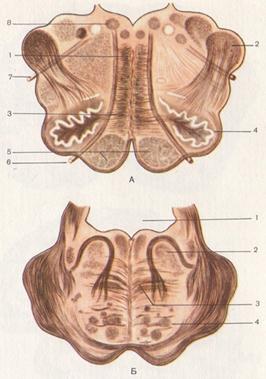

Необычные объекты: Переднее продырявленное вещество

Раздел: Альбом открытий